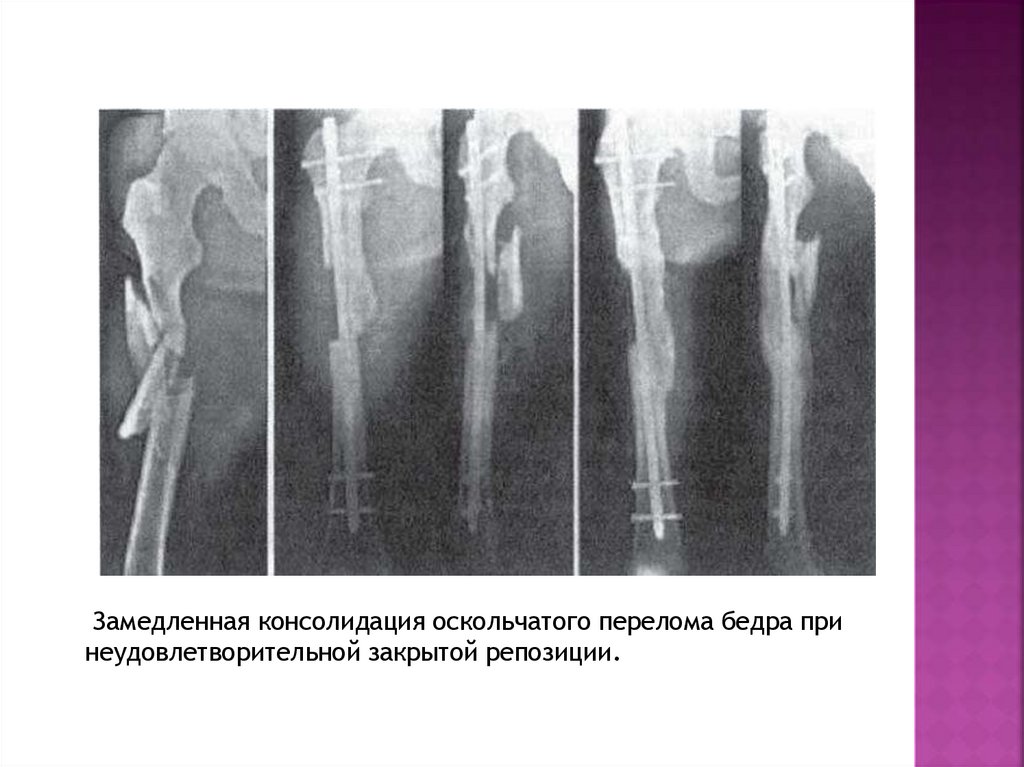

Замедленная консолидация оскольчатого перелома бедра при

неудовлетворительной закрытой репозиции.